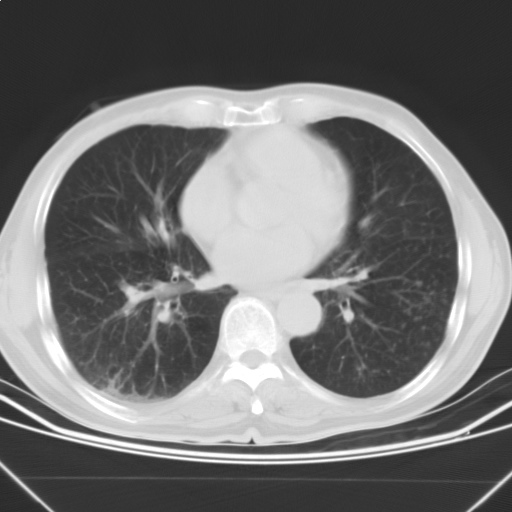

以下是引用随光逐影在2009-5-1 13:53:00的发言:[br]考虑为:1)两肺血行播散型肺结核;2)右肺下叶炎症感染。3)右侧胸膜增厚。